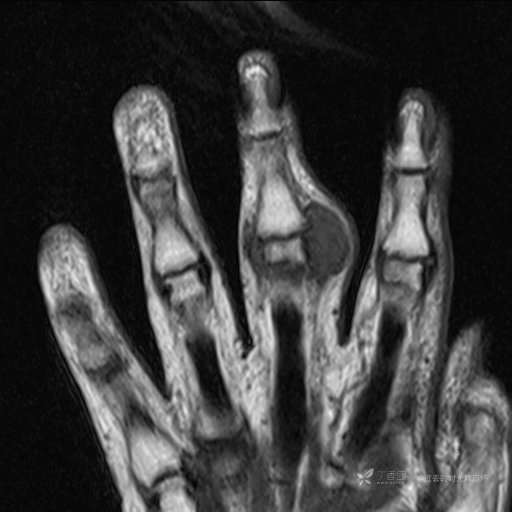

患者性别:女

患者年龄:59岁

主诉: 手指肿胀2年,其间明显肿胀,抗炎后肿胀减轻,近几日肿胀疼痛加重。

T2及T2压脂

T1

DWI ADC

预扫

增强

提示:小指是伪影。